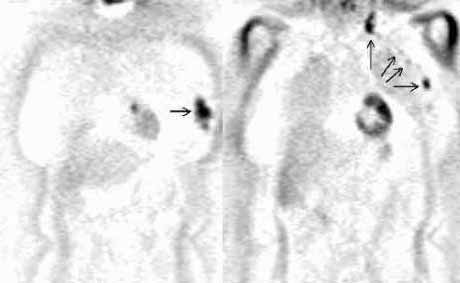

Рис. 4. Применение позитронной эмиссионной томографии при раке молочной

железы. Множественные очаги гиперфиксации 18F-ФДГ в у пациентки с аденокарциномой

левой молочной железы и метастазами опухоли (фронтальные срезы).

Слева. Срез на уровне молочных желез. Стрелкой отмечена злокачественная

опухоль левой молочной железы.

Справа. Срез на уровне сердца. Стрелками отмечены множественные метастазы

в региональных лимфатических узлах.